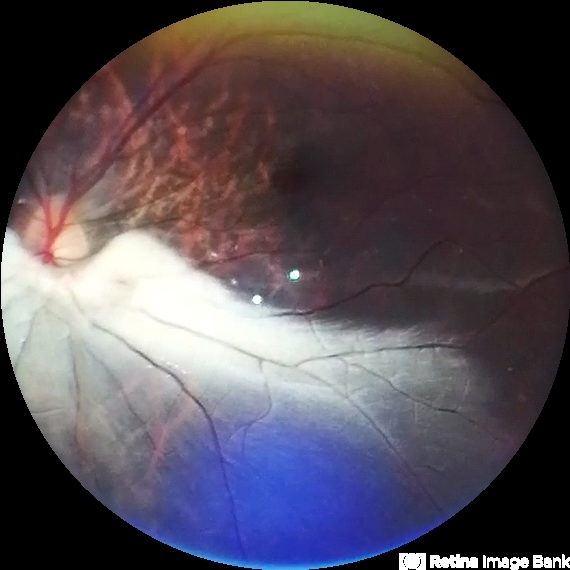

- Fundus photograph of an 35-year-old woman with myelinated nerve fiber layer

- myelinated nerve fibers